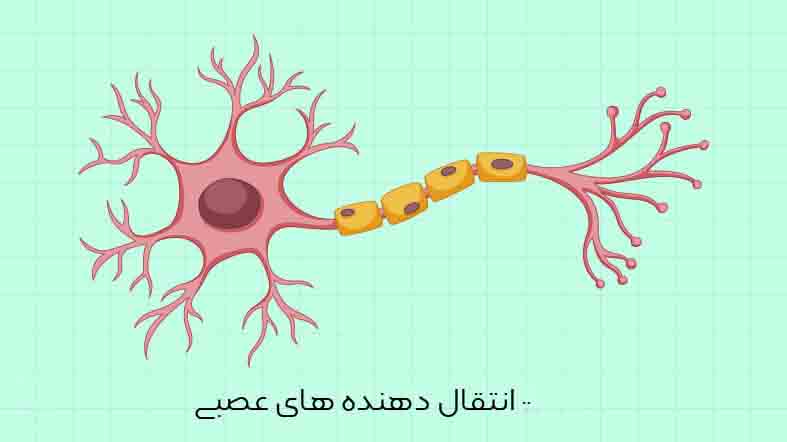

قیمت: 22٬000 تومان - دسته بندی فایل: پاورپوینتپاورپوینت پیک های عصبی یا انتقال دهنده های عصبی

فروش ویژه پاور پوینت حرفه ای پیک های عصبی یا انتقال دهنده های عصبی با تخفیف استثنایی فقط 19 هزار تومان تعداد اسلاید: 9 اسلاید